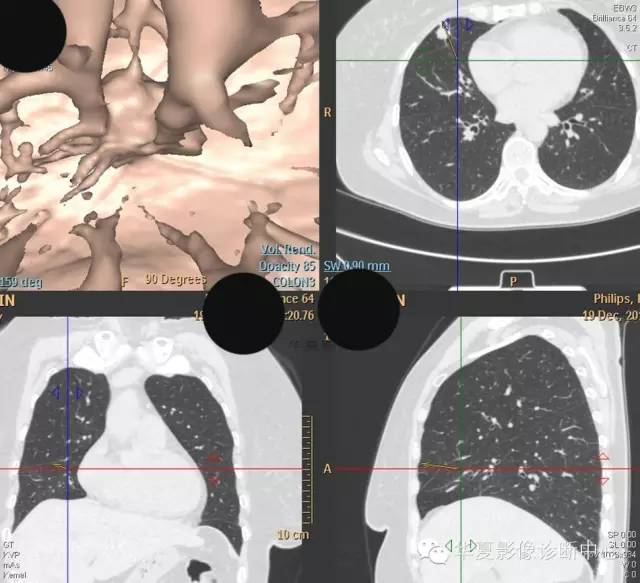

【病例学习】典型周围型肺癌CT病例一例

女,56岁,其父因肺癌去世,自觉胸部疼痛不适来诊要求拍胸片。

检查所见:

1.右肺上叶:肺组织1块,大小13×4×7cm。切面棕红色。2.右肺上叶肿物:灰白色组织一块,大小3×1×1.5cm。切面灰白色。3.右肺中叶结节:灰白色绿豆大组织1块。4.淋巴结:灰黑色绿豆大组织1块。

检查结论:

(右)肺中分化鳞状细胞癌。浸及胸膜。支气管残端切净。淋巴结未见癌转移(0/10)。